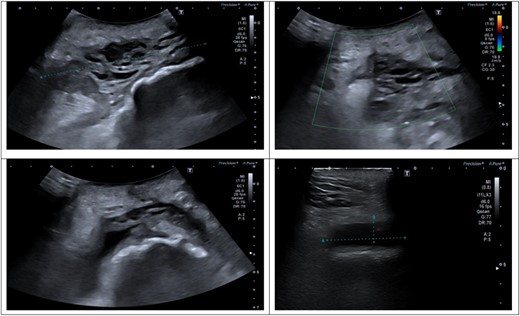

An ultrasound scan of his hip and thigh was performed which showed a large 10.1 cm × 4.3 cm, complex collection with mixed solid/cystic components. This was associated with a tract extending from the skin surface and a deeper fluid collection that tracked along the posterolateral right femoral shaft (Fig. 3). A subsequent CT femur with contrast reported a large collection adjacent to the greater trochanter with no evidence of fistulous communication with the joint. A separate locule of fluid 2.5 cm in length was seen superior to this and communicated with the main collection. There was no sign of prosthetic loosening or radiological evidence of osteomyelitis (Fig. 4).

(A–D) Ultrasound scan of right hip and thigh showing a large 10.1 × 4.3 cm complex collection with mixed solid/cystic components. There was no internal vascularity. This was associated with a tract extending from the skin surface and a deeper fluid collection that tracked along the posterolateral right femoral shaft. There was significant oedema of the subcutaneous tissue overlying the hip and thigh.